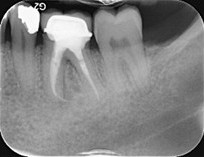

Fractured file removal and re-rct

Pre-op